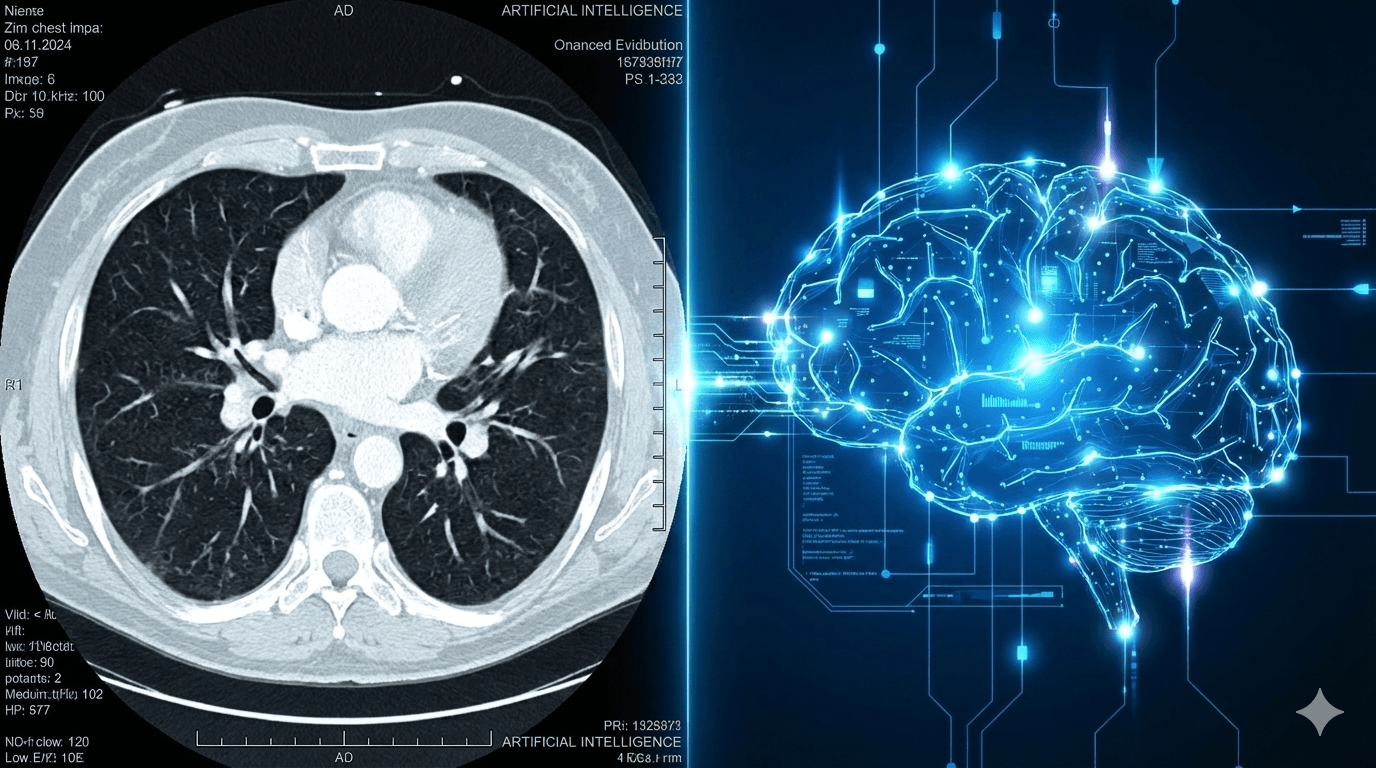

By analyzing X-ray and CT images, the AI-enabled workflow is designed to help radiologists spot subtle lung nodules that are often missed by the human eye.

The collaboration will utilize FDA-cleared radiology AI algorithms through Microsoft’s Precision Imaging Network, a platform currently used by more than 80% of U.S. hospitals.